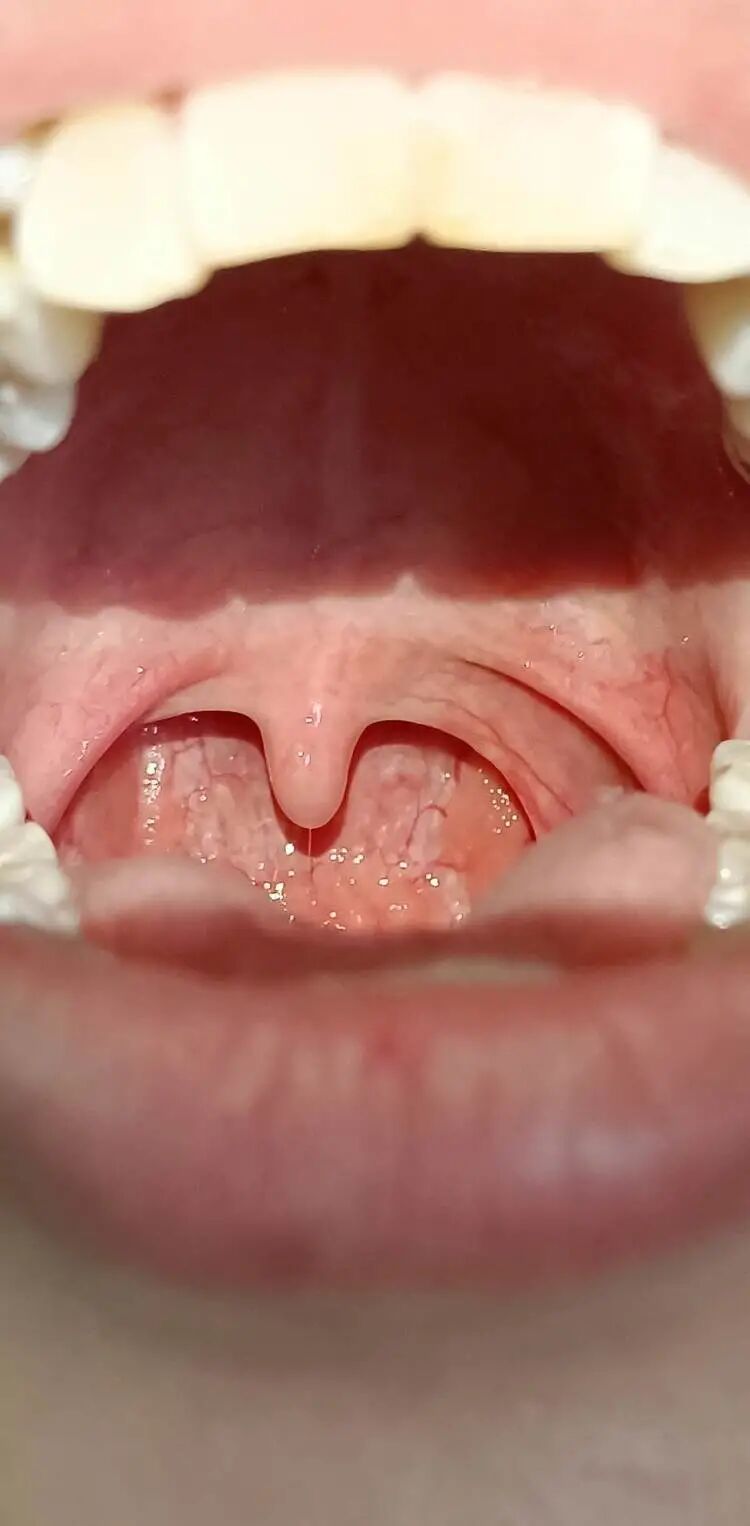

1、采集者用压舌板辅助,快速查看患者口腔黏膜和咽部情况,被采集者张口发“啊”长音,悬雍垂上提暴露咽后壁,拭子越过舌根,到达咽部,快速擦拭两侧扁桃体和咽后壁分泌物,擦拭时充分接触粘膜。

1、做核酸检测前对镜练习,调整好舌体位置,使咽腔完全暴露出来,便于采集者操作。